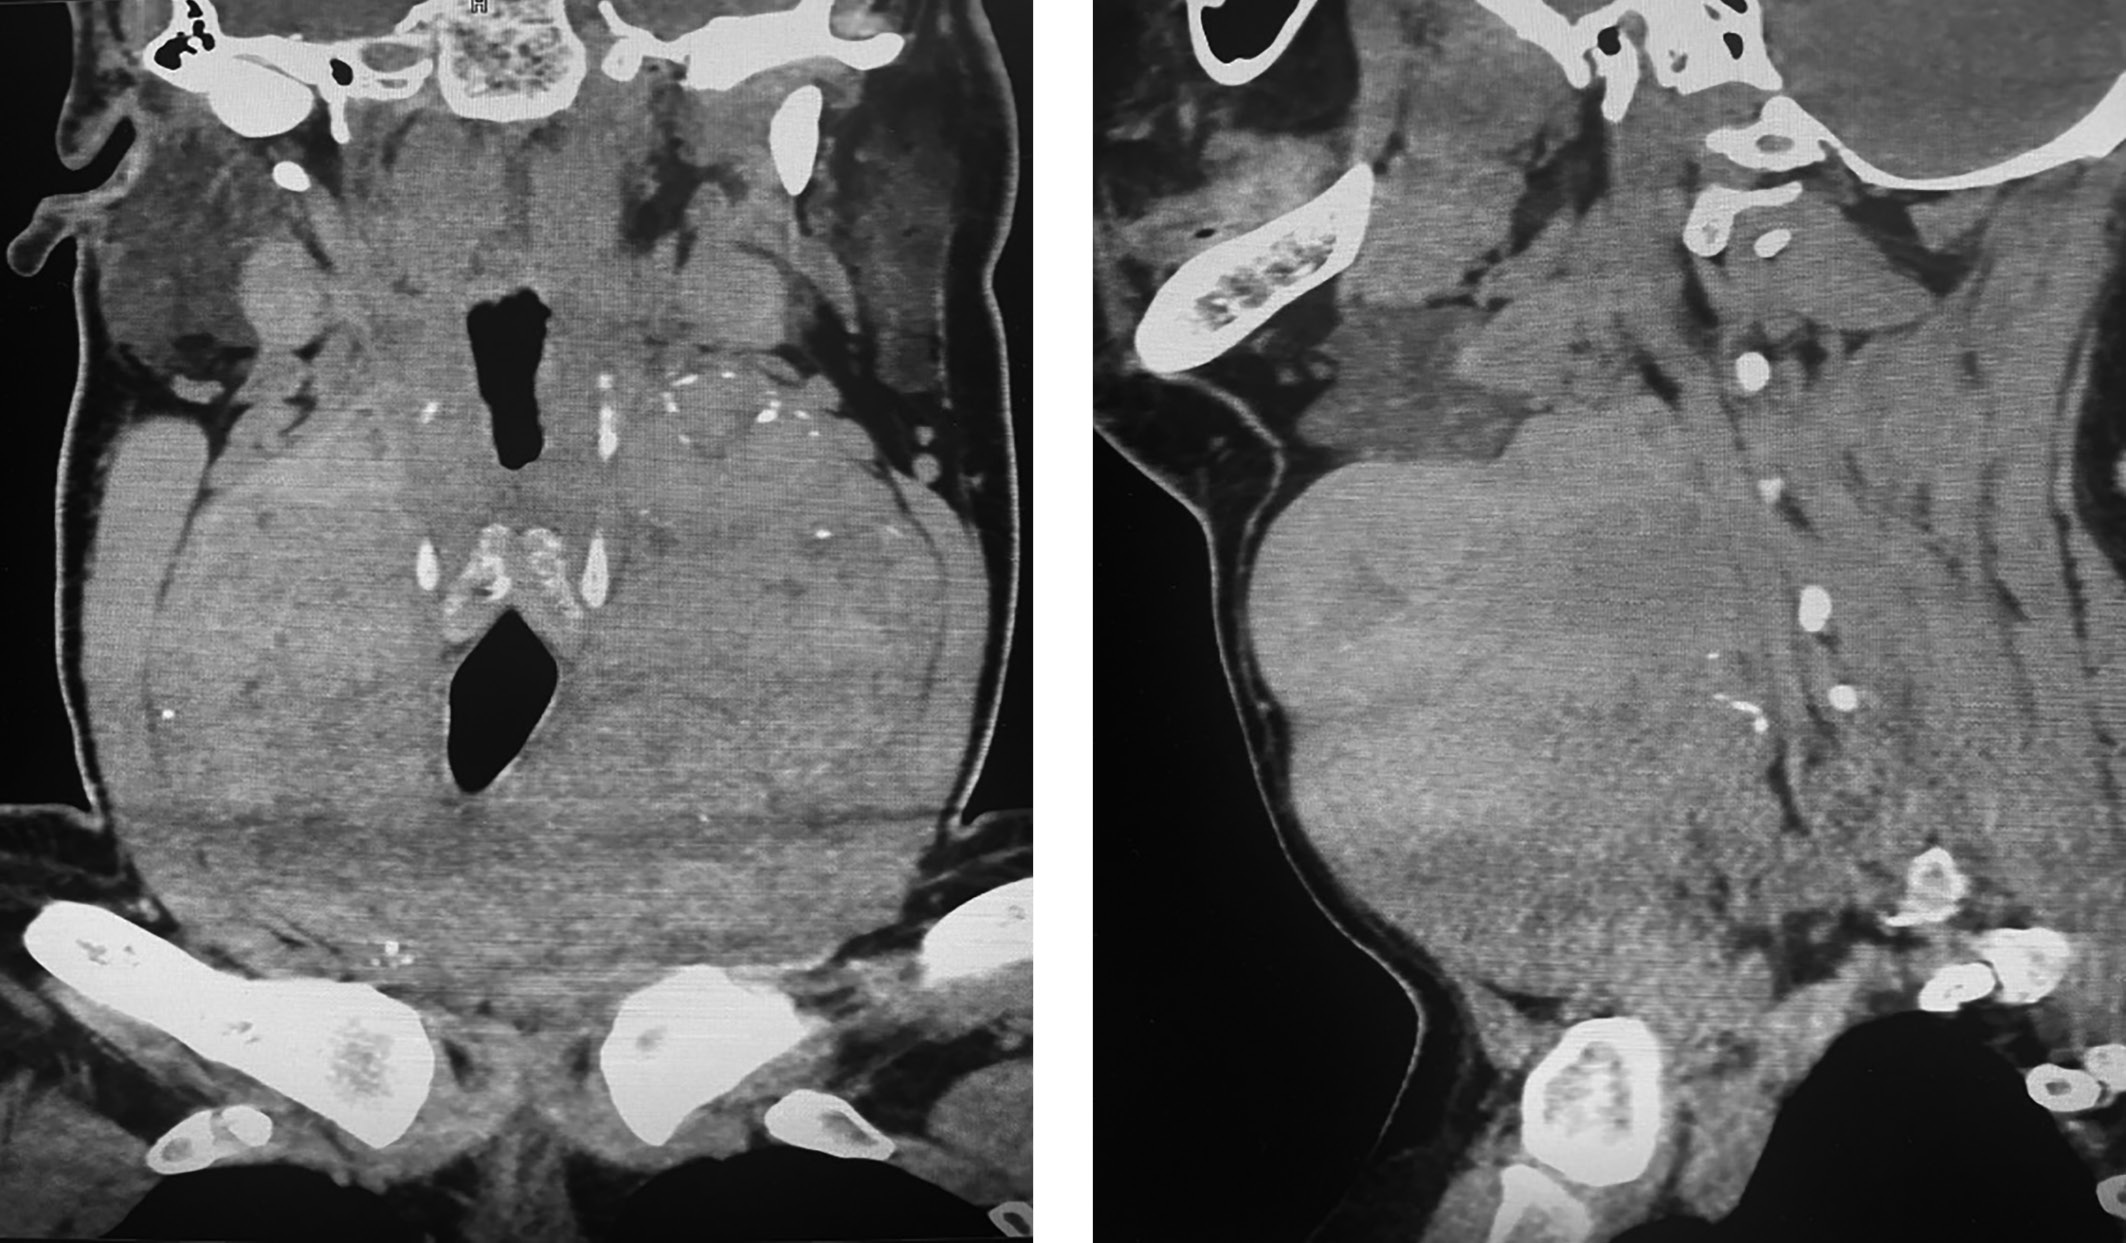

2. Рис. 2. Снимок компьютерной томографии | |